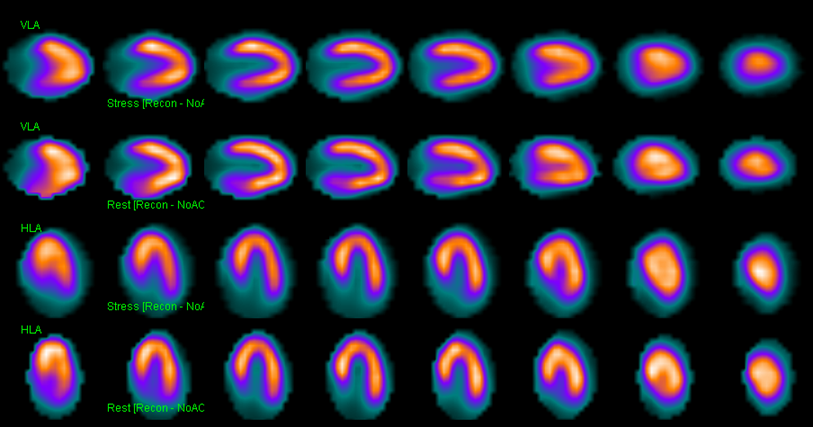

Molecular Imaging Webinar SeriesA 4-part webinar series in partnership with the Philippine Society

of Nuclear Medicine on November 18, 25, December 2, and 9, 2021